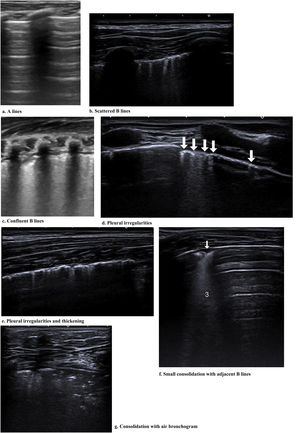

Fig. 2 shows the main findings of the LU imaging described in the study.

Most of the studies under analysis had LU findings in common in the presence of SARS-CoV-2 infection. The most common finding was B lines, which had very distinct characteristics, 34 of which reported focal, diffuse and confluent B lines.12,15,18,19,25,26,27,29,30,31,32–35,38,62,67,68,70,72–74,77–88 Twenty-nine studies described consolidations of different types: small, large, linear, subpleural, multifocal and translobar,12,15,18,19,25,26,27,29,30,33,35,38,62,63,67,68,70,72,73,75,78–80,82–85,87,89 associated with white lung12,30 and with air bronchograms18,38. Nineteen studies described pleural irregularities,12,15,18,26,27,30,32,33,35,62,70,72,77,79,80,82,84,85,89 and 19 reported pleural and subpleural line alterations, such as thickening or shred sign.18,19,26,29,31,32,34,38,62,67,70,72,73,75,77,80,85 Ten studies referred to pleural effusion,38,62,67,70,72,75,77,82–84 8 reported bilateral findings15,34,63,79,82,86,87,88 and 3 revealed preponderance of compromise in posterior areas.79,80,89 Three studies associated appearance of A lines during recovery 35,67,80 and most of the papers reported the LU role in the serial evaluation of patients with COVID-19.27,29,30,33,35,67,68,70,71,72,74,75–77,80

Other characteristics found were the presence of glass rockets38 with or without the Birolleau variant,26 also known as white lung.61